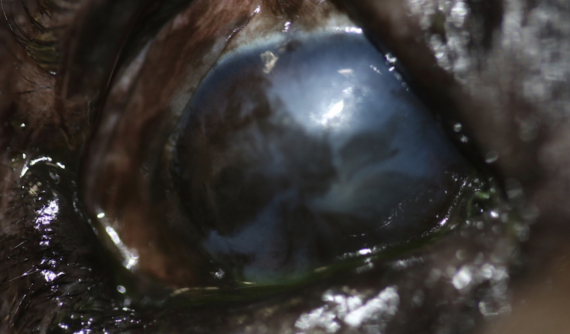

El tratamiento del carcinoma consiste en su extracción de la superficie ocular mediante una cirugía llamada queratectomía.

Al ser el ojo un sitio complicado para quitar buenos márgenes que permitan garantizar que no quedan células tumorales residuales, se utiliza la crioterapia para congelar y destruir estas células en los bordes de la herida tras la excisión del tumor. Además, se pueden utilizar algunos medicamentos quimioterápicos tópicos durante la cirugía o en el post operatorio como la Mitomicina C.

En el caso de Brutus, tras la cirugía de queratectomia aplicamos la crioterapia. La herida ha cicatrizado muy bien y por ahora no hay ningún signo de recidiva.

Gracias a este procedimiento, Brutus ha recuperado la mayor parte de su visión en este ojo .